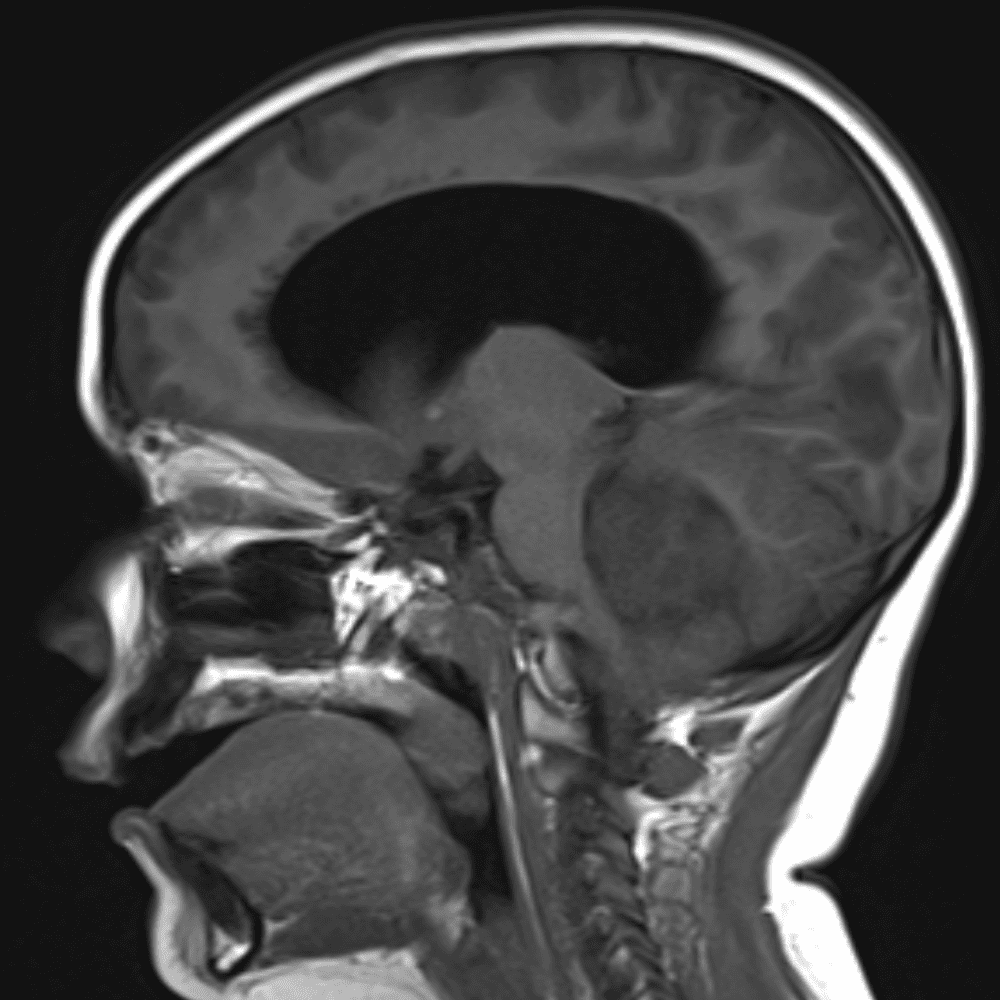

๋‹น์ง ์‹œ ํ”ํžˆ ๋ณผ ์ˆ˜ ์žˆ๋Š” ์‚ฌ๋ก€์˜ ์ „ํ˜•์ ์ธ ์˜ˆ๋ฅผ ํฌํ•จํ•ฉ๋‹ˆ๋‹ค.

39 ์‚ฌ๋ก€